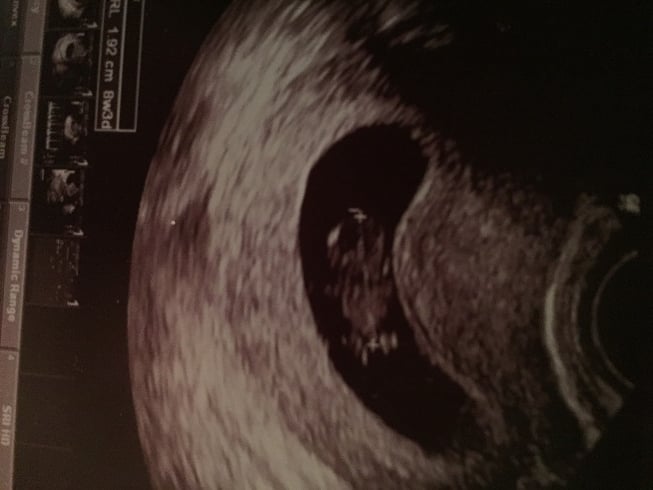

Transvaginal at 7w1d. And I know the yolk sac is on the right because my hubby asked if it was the head and they said yolk sac. ) so would that make it boy??

Second picture is 8 weeks 1 day also transvaginal